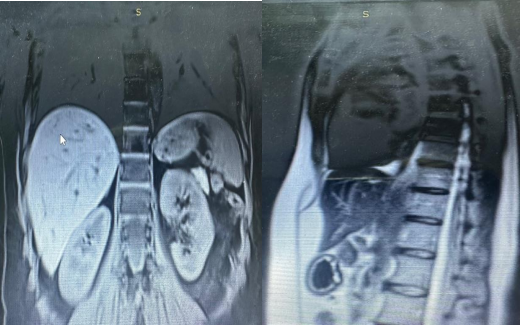

In june 2024, an abdominal MRI was performed, without notable particularities in the oncological context (Figure 9).

Figure 9: Abdominal MRI